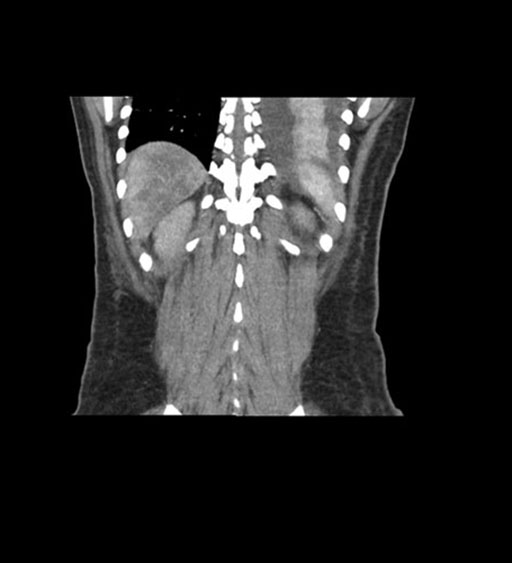

Coronal Arterial

Coronal Venous